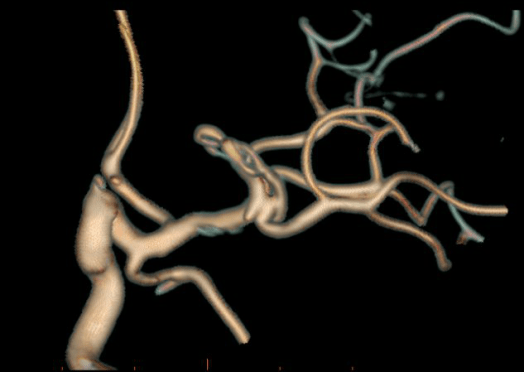

Clipping di aneurisma complesso M1-M2 di sinistra – ricostruzione biforcazione arteria cerebrale media

Aneurisma Biforcazione ACM – Vito Fiorenza